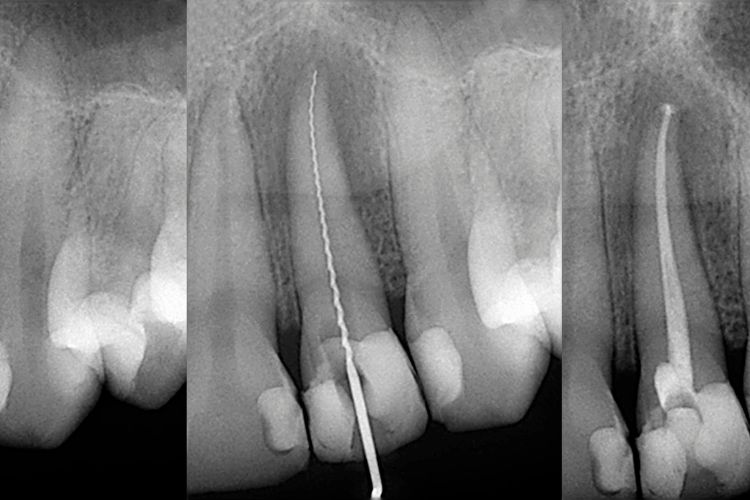

La endodoncia es un procedimiento odontológico que permite conservar un diente dañado o infectado, en lugar de extraerlo. Básicamente, consiste en retirar la pulpa dental (el tejido nervioso y vascular que está dentro del diente), limpiar la zona afectada y sellarla de manera segura para evitar que vuelva la infección.

Reconstrucción con poste de fibra de vidrio

Si el diente ha perdido mucha estructura, se coloca un poste dentro del conducto tratado. Este refuerza el diente y sirve de soporte para la reconstrucción. Es una opción muy utilizada por su resistencia y estética.